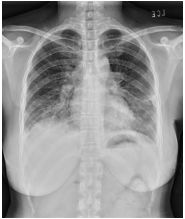

4. 39 y/o female, productive cough for 2 months